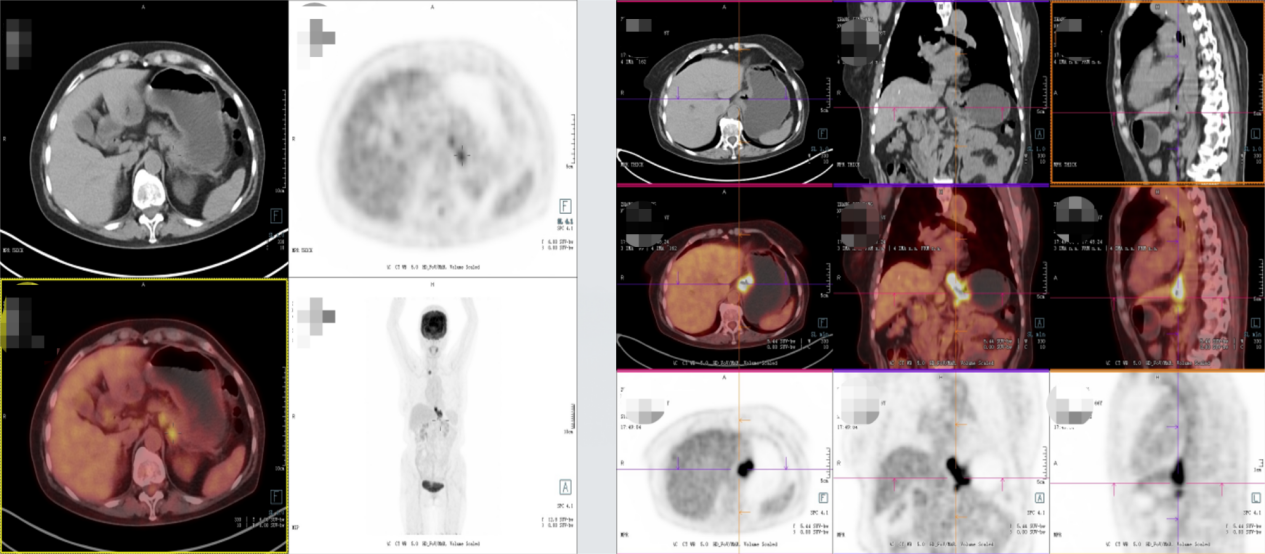

2025年11月19日复查影像学显示,贲门癌化疗后,贲门胃壁稍增厚;贲门部肿物及转移淋巴结较前明显退缩,影像表现为接近CR(无可评价病灶)。

MDT讨论:影像科:患者目前肿瘤退缩明显,影像表现接近CR(无可评价病灶),可进一步完善PET检查。肿瘤科:患者目前疗效评估部分缓解(PR),有CR可能,可继续维持原方案化疗,可完善胃镜检查多点取病理,以评估是否达CR。普外科:患者免疫治疗效果理想,目前肿瘤退缩明显,有手术指征,可考虑行手术治疗。消化科:患者单次PD1治疗即出现重度免疫性肝炎,虽经短暂激素治疗后即好转,但不排除PD-L1治疗后再次出现免疫性肝炎,需密切监测其肝功能变化。